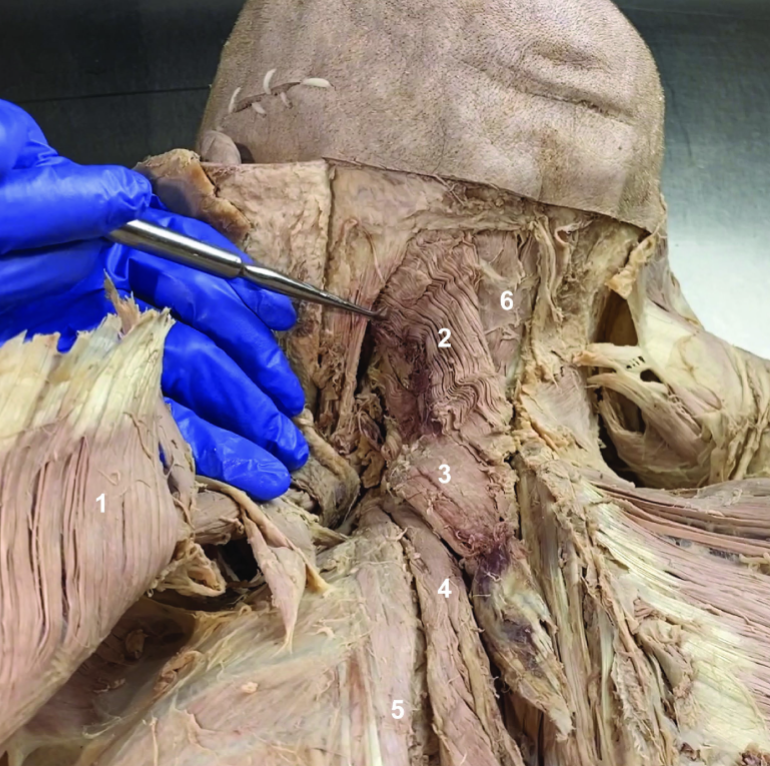

Trapezius (reflected)

ID structure

Spinal accessory n. (CN XI)

ID structure

Transverse cervical a.

ID structure

Levator scapulae

ID structure

Rhomboid minor

ID structure

Rhomboid major

ID structure

Rhomboids (reflected)

ID structure

Splenius capitis

ID structure

Splenius cervicis

ID structure

Longissimus

ID structure

Iliocostalis

ID structure

Semispinalis capitis